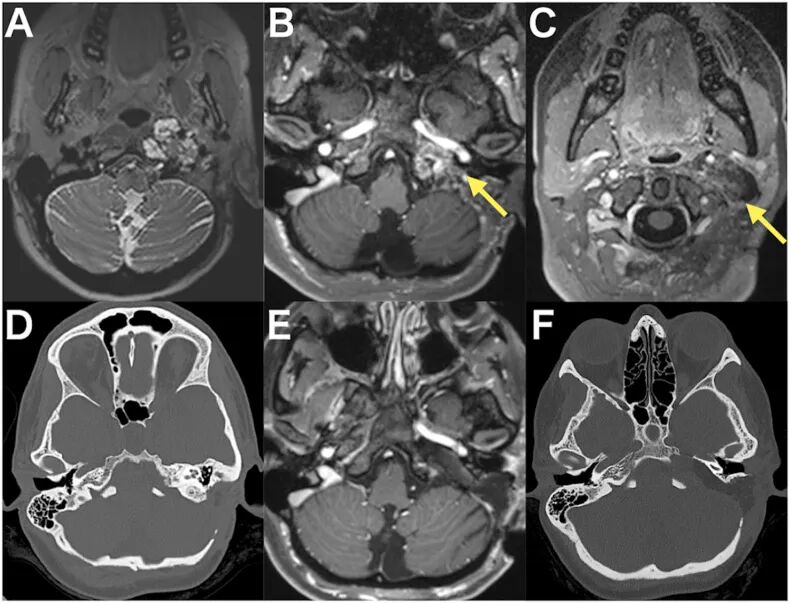

图1,A:术前T2加权MRI显示高信号的颈静脉孔区肿瘤。B和C:术前钆增强T1加权MRI显示肿瘤呈部分强化,从岩尖延伸至颈部区域(箭头所示)。D:术前CT扫描显示岩骨内病理性骨质改变。E:术后钆增强T1加权MRI确认了肿瘤的近全切除。F:术后CT扫描显示手术径路,突出显示已被磨除的岩尖。

手术在 颅神经VII、IX、X、XI、XII 的电生理监测下进行。采用 前外侧入路 暴露颈内静脉和颈内动脉,发现颈内静脉受侵。显微镜下切除了从颈部区域延伸至颈静脉孔的肿瘤。随后,磨除前次手术遗留的残余乳突骨质,暴露 后半规管、面神经管和颈静脉球 。运用e-TIA,识别出 内听道和耳蜗 ,并在内镜直视下进一步磨除岩骨,从而到达位于岩尖的肿瘤。肿瘤切除及病理性骨质去除后,颈内动脉的水平段和垂直段,以及 Meckel腔均得以暴露。通过前外侧通道置入30°内镜,可直视Meckel腔内的 三叉神经 。

术后影像显示肿瘤 近全切除 (图1E)。CT显示岩骨被广泛磨除,但未损害下方关键的骨性结构(图1F)。患者术后恢复良好,无神经系统并发症。听力功能得到保留,吞咽困难通过物理治疗后得到改善,患者于术后第11天出院。术后病理为脑膜瘤。患者术后还进行了质子治疗,1年后随访无复发迹象。